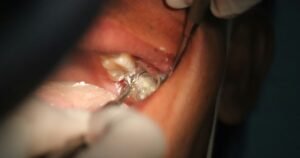

cancer-de-boca-diente-muela

Unsplash/Mufid Majnun